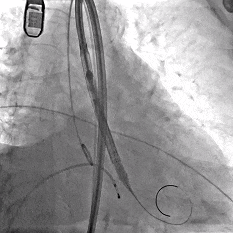

缓慢脱钩

瓣膜无位移

脱钩后造影

瓣膜位置可,无瓣周漏

左冠切线造影,瓣膜同轴性佳,位置可,无瓣周漏

术中最关键环节在于瓣膜的精准定位与稳定释放。ScienCrown瓣膜系统的“全释放/全回收”功能,允许术者在最终释放前,更充分地评估调整瓣膜的定位与稳定性,极大提升手术容错率与安全性。